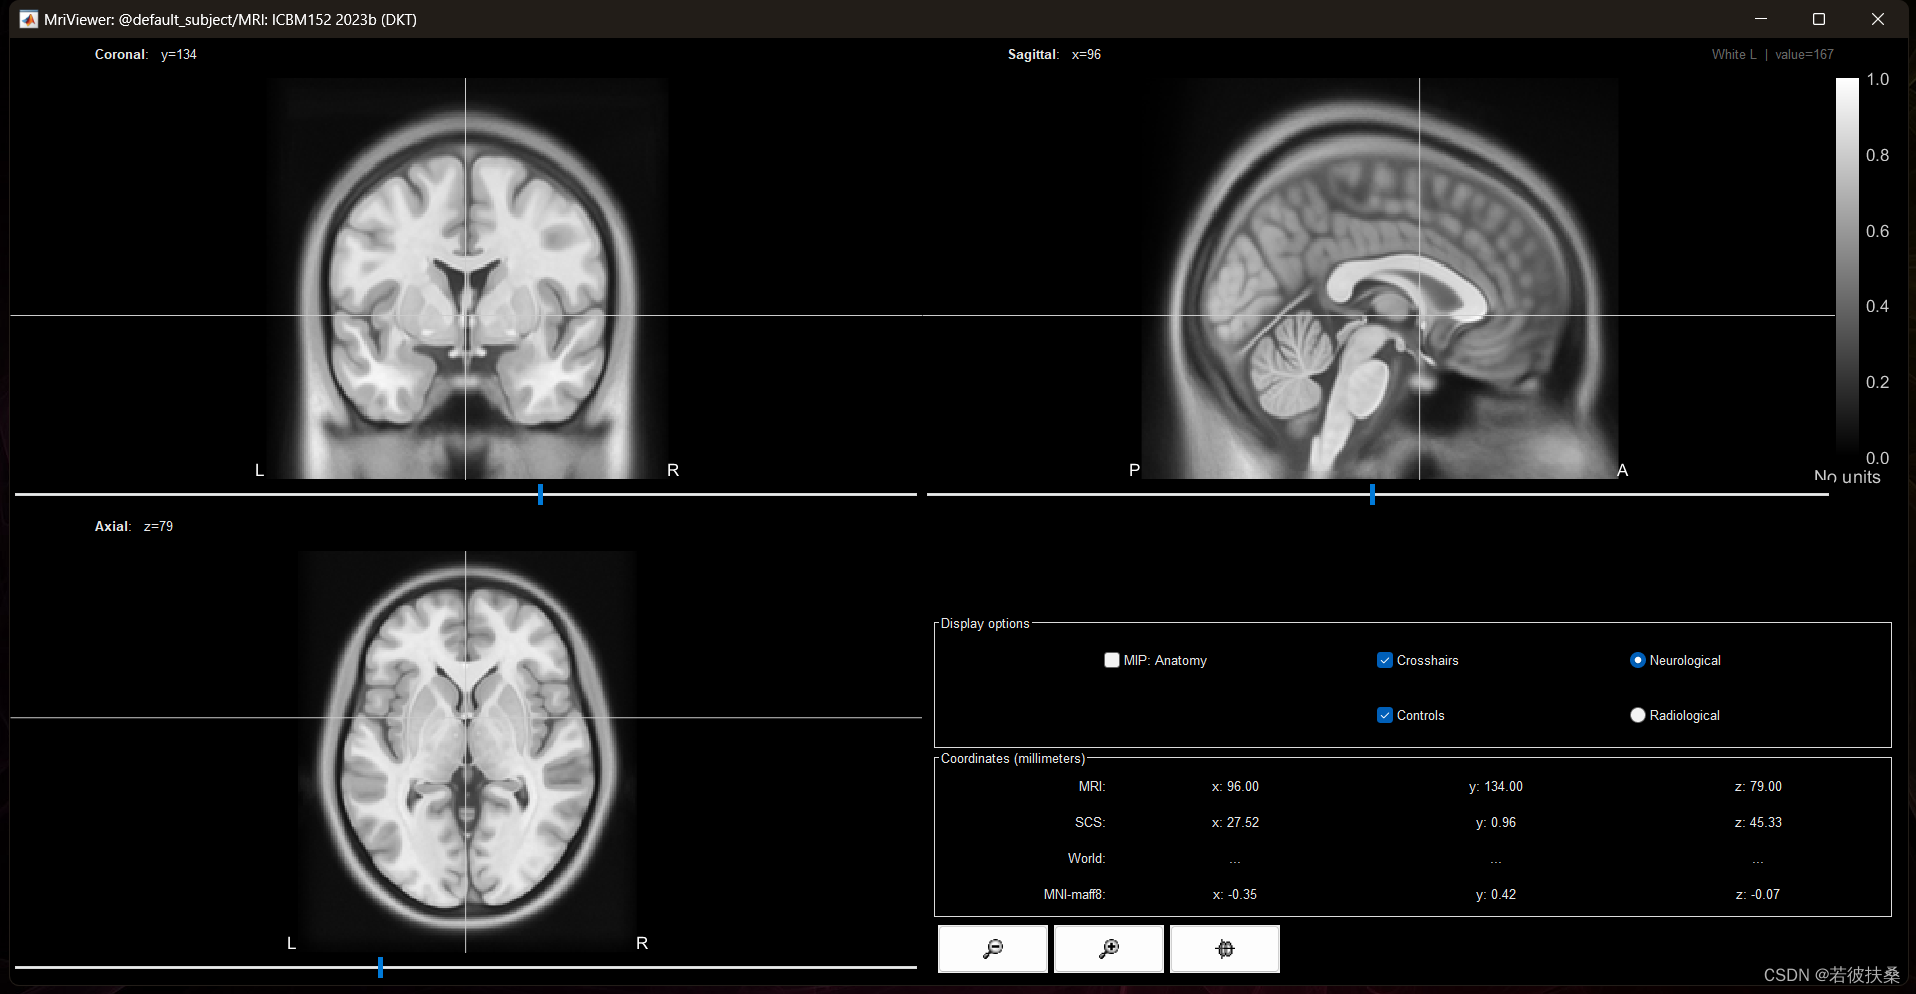

4. 双击绿色的“MRI”即可打开,其他的可以自行尝试。后续我们源分析也主要是用标绿的这些文件作为结构数据。